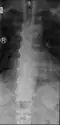

Ossification of the posterior longitudinal ligament in DISH -